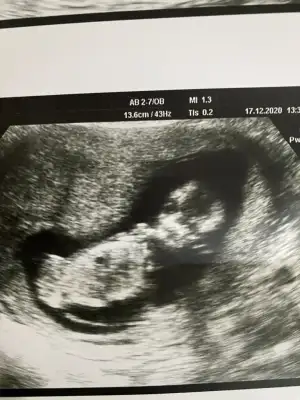

canım senin attıgın usg de bebegi yandan görüyoruz ya ben kız gibi hissettim inan icimden öyle geldi kendi usg görüntülerime baktım video dan hep bir cıkıntı var bana erkek dendi 12. hafta dan beri sana erkege benziyor derken bacaklarının arasını gösterdi mi dr şuan pc den yazıyorum telden girip 14. hafta daki usg bacaklarının arasını atıcam hala senin kızın olucak gibi geliyor bana hayırlısı ama öyle geliyor ne yapayım :)

Yok canım benim oranda vermedi pipi de göstermedi ondan kafam karıstı yan yatiyo dedi görünen şey kordonda olabilir pipi de 16. Haftada tam belli olur dedi ben yüzde birlik ihtimalde olsa soylemeliyim dedi ondan kafam karıstı

Oran da vermeyince yani bildiğin diğer erkek gibi dediyse değiebilir o benim usg görünce kız doğdu içime

usg gören herkes kıza benziyor yandan dedi ama bilemiyorum